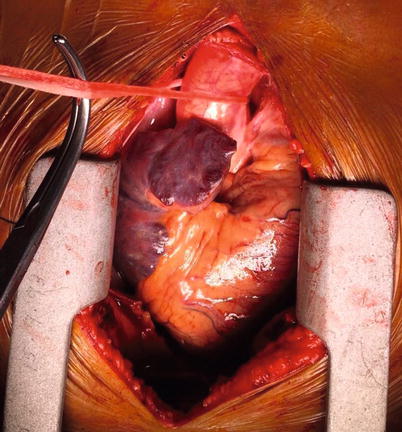

Fig. 37.4

Curly-Semb vascular clamp passed behind the ascending aorta in the transverse sinus